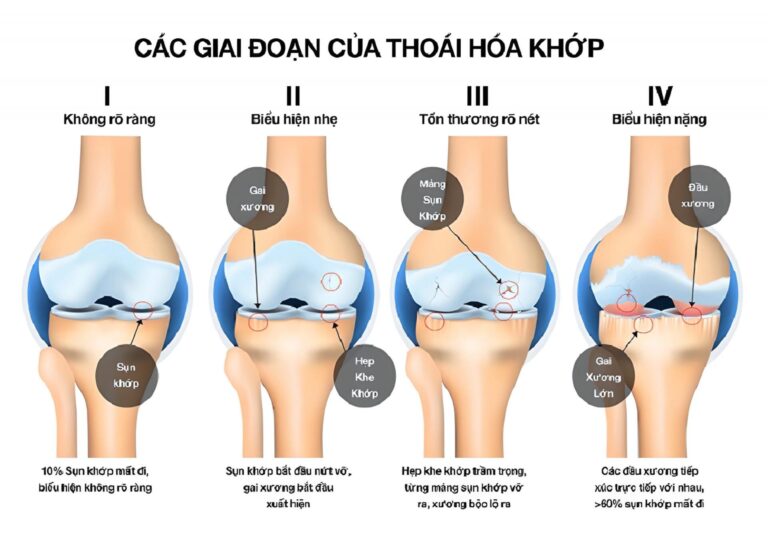

Mặc dù thoái hóa khớp gối không đe dọa tính mạng, nhưng nếu bệnh tiến triển đến giai đoạn nặng, nó có thể gây tàn phế. Do đó, thường xuyên thăm khám sức khỏe xương khớp giúp tầm soát bệnh sớm và xác định mức độ thoái hóa để bác sĩ đưa ra phác đồ điều trị phù hợp: